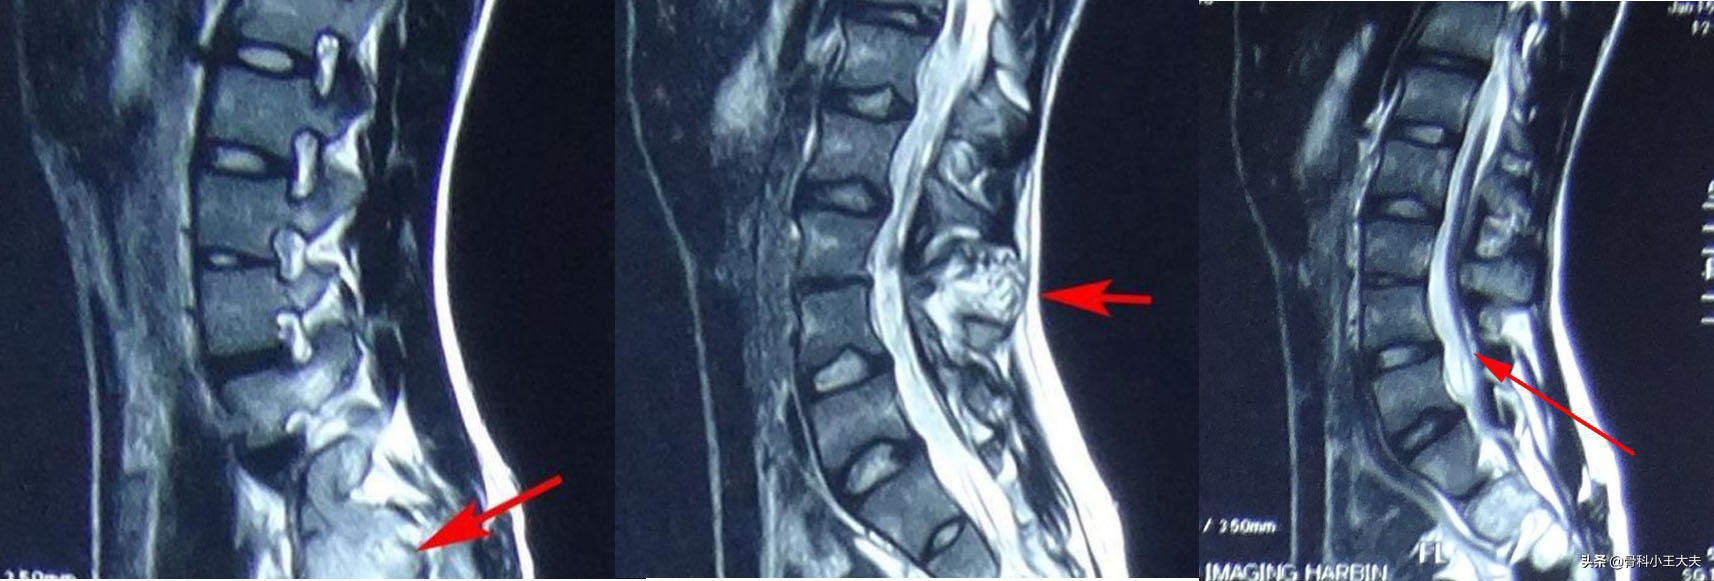

患者腰骶部存在一个团状异常信号,有可能是脂肪瘤甚至畸胎瘤,同时合并硬脊膜膨出。此外MRI显示患者的脊髓并没有随着生长发育向上移动,而是与远端“有所牵挂”,腰部的神经像一根根弓弦与远端相连,也就是医学上所称的“脊髓栓系”。患者二便*禁失**很可能就是由于身体逐渐长高,产生脊髓栓系后导致的。

手术不仅要解决侧弯,还要减压神经,解除栓系,改善神经功能。